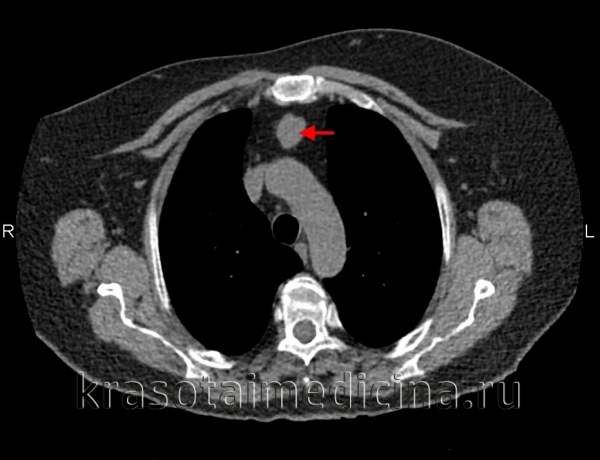

Рентгенологическое исследование: срединная тень почти на всем своем протяжении расширена в обе стороны за счет патологического затемнения, занимающего большую часть переднего средостения. Это интенсивное, неоднородное затемнение имеет дольчатую форму с бугристыми четкими контурами, расположенными местами (справа) в виде «кулис». На жестком снимке с передержкой и на томограммах более отчетливо выявляется дольчатый характер патологического образования и узлы, расположенные на различной глубине, видны также неизмененные трахея и главные бронхи. Пищевод не изменен.

Очаговых и инфильтративных изменений в легких не определяется. Куполы диафрагмы подвижны, синусы свободны. Корни легких, сердце и аорта не определяются из-за наложения на них описанного затемнения.